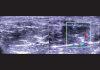

Diabetic myonecrosis is an underreported complication of long-standing, poorly controlled diabetes mellitus which is usually self-limiting and responds well to conservative management. Patients frequently have microvascular complications, and although short-term prognosis is good, the long-term prognosis is poor. We report four cases of diabetic myonecrosis admitted in a tertiary care hospital.